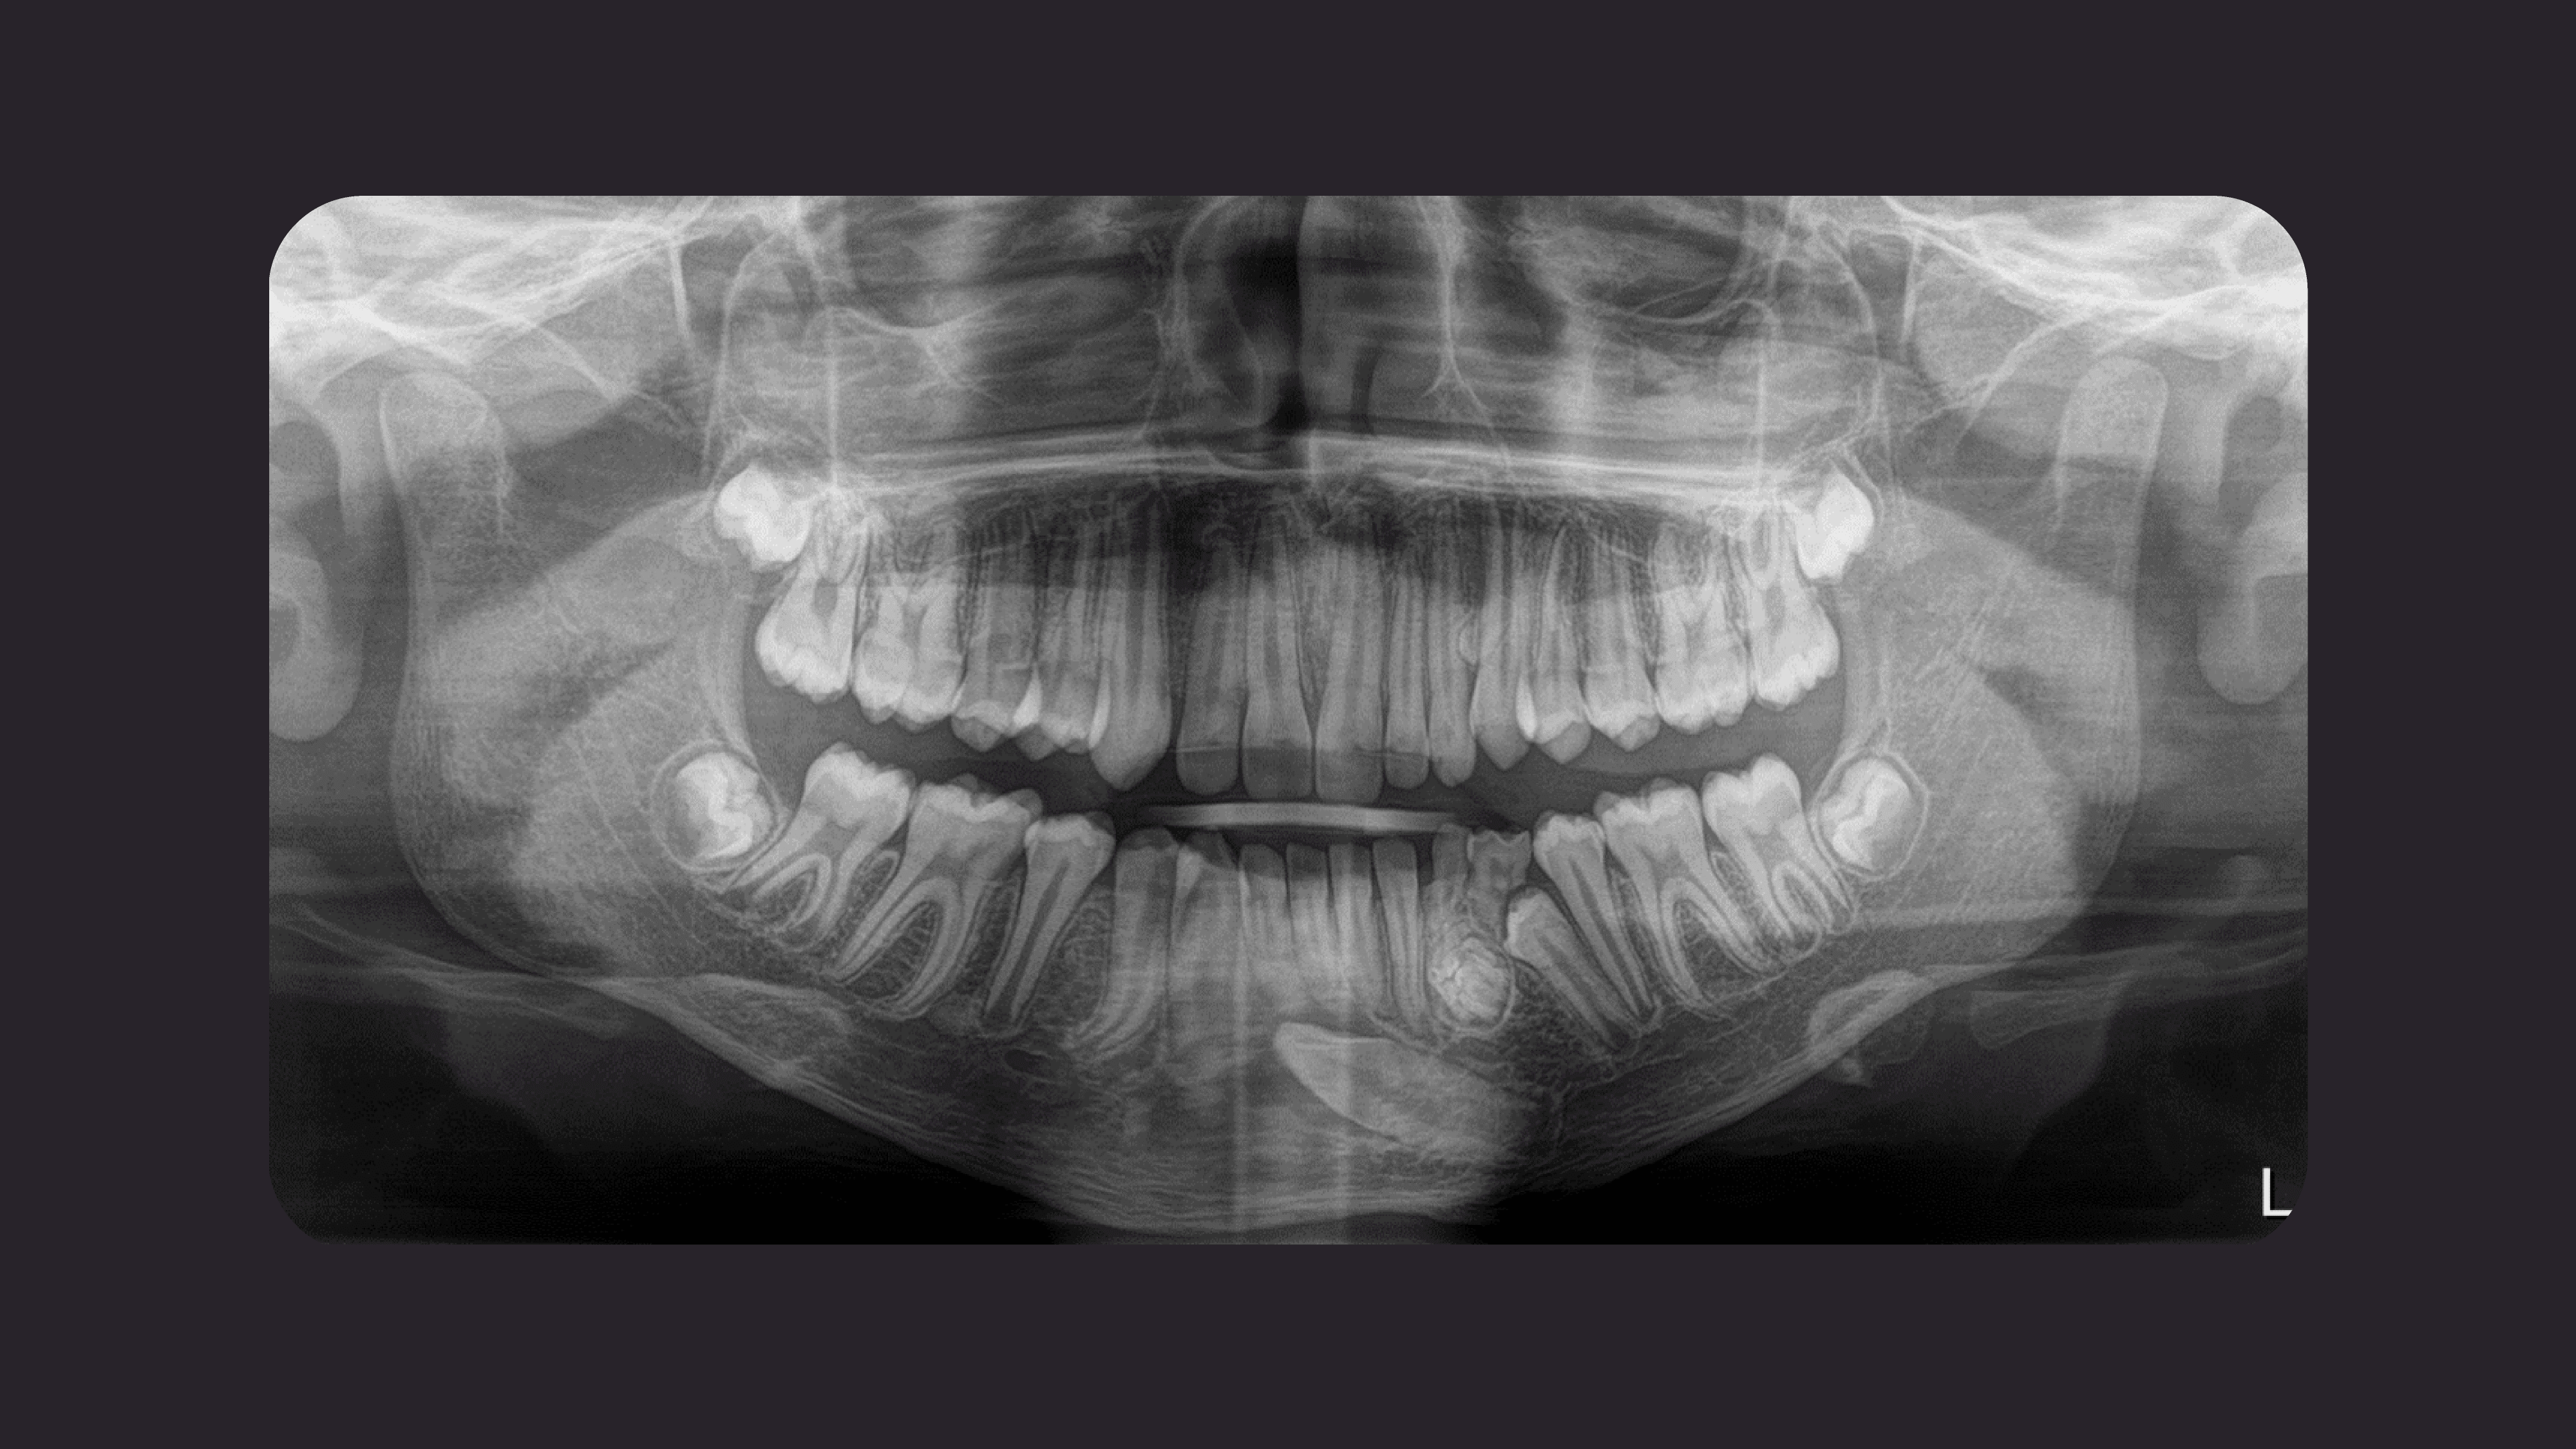

Figura 1

Fig.1: Quiste dentígero asociado a pieza supernumeraria.

Al evaluar la radiografía panorámica se observa persistencia de pieza deciduas, múltiples piezas permanentes impactadas. Disminución en la densidad ósea con adelgazamiento de sus cortical de la basal mandibular. Imagen radiolúcida a nivel coronario de pieza 2.2 a descartar lesión quística.